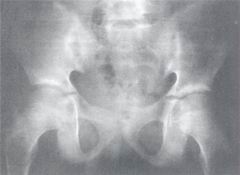

幼年型類風濕性關節炎 X線表現X線檢查:早期可見關節附近軟組織腫脹,骨骺部骨質稀疏。晚期嚴重關節炎患者可見骨表面破壞,關節腔變窄,骨囊性變,骨膜反應及關節半脫位等。